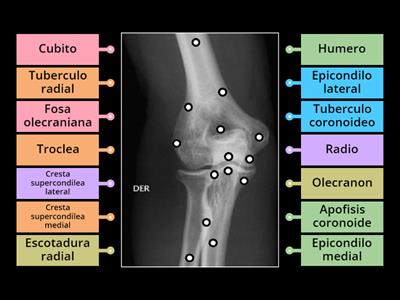

Anatomia rx codo ap